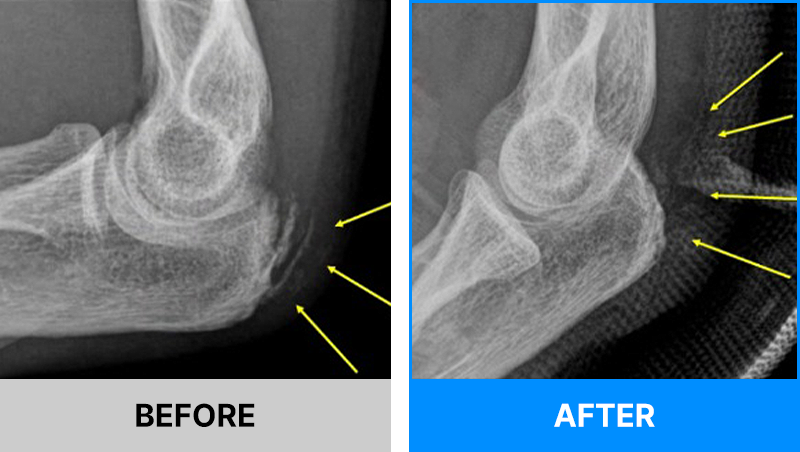

즉시 일상 여러 원인으로 견관절 관절막이 두꺼워져 모든 범위로의 관절범위 제한과 심한 통증이 동반되는 질환입니다.

관절가동술과 수압팽창술은 오십견(동결견) 치료에 굉장히 효과적인 비수술 치료법입니다.

염증치료제와 유착방지제를 중요 위치에 주입하여 굳어진 근육과 관절을 이완시키고,

통.증.없.이.절.개.없.이. 전문의가 직접 관절을 풀어주어 굳어진 관절막을

부드럽게 풀어주어 굳은 어깨 관절의 움직임을 정상 범위로 되돌리는 치료법입니다.

오십견이 오래되면 관절막 자체가 굉장히 두꺼워집니다.

이렇게 두꺼워진 관절막은 스트레칭만으로 늘어나고 얇아지기가 임상적으로 매우 힘듭니다.

이 상태에서 단순히 주사치료만 받는다면 일시적인 통증 완화에 그치는 대증치료에 불과합니다.

관절의 움직임이 제한된 상태에서는 통증이 반복될 가능성이 매우 높습니다.

관절막을 모든 범위로 충분히 풀어주게 되면 시술 직후 95% 이상의 관절범위를 바로 얻을 수 있고 통증도 바로 좋아지게 됩니다.